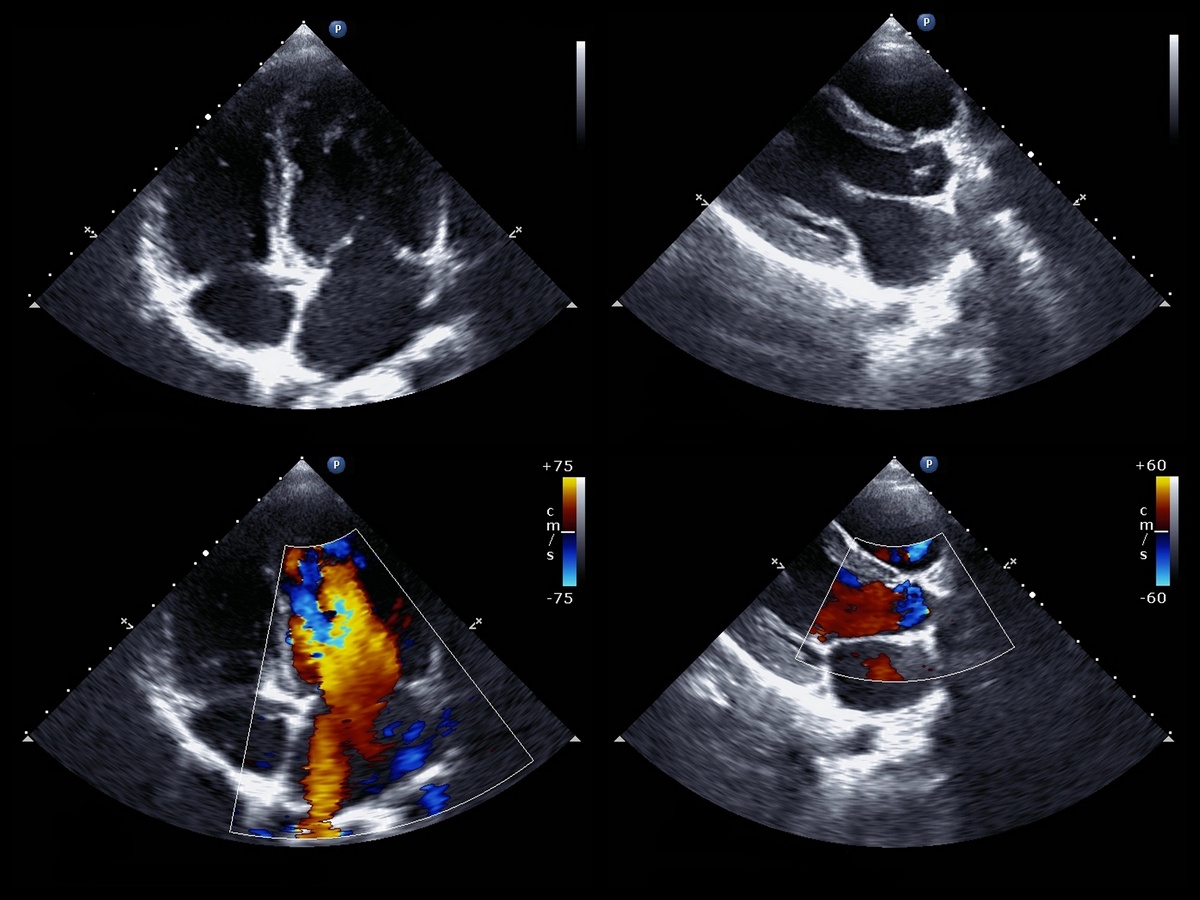

Эхокардиогра́фия (греч. ἠχώ — отголосок, эхо + καρδία — сердце + γράφω — писать, изображать) — метод ультразвукового исследования, направленный на исследование морфологических и функциональных изменений сердца и его клапанного аппарата (Эхокардиография — Википедия ).

Если говорить простым языком, это УЗИ сердца, точно такое же, как и УЗИ печени, щитовидной железы и др. ЭхоКГ позволяет врачам получить полную картину о состоянии вашего сердца, оценить его структуру, размеры, состояние клапанов и крупных сосудов (аорты, легочной артерии, нижней полой вены).